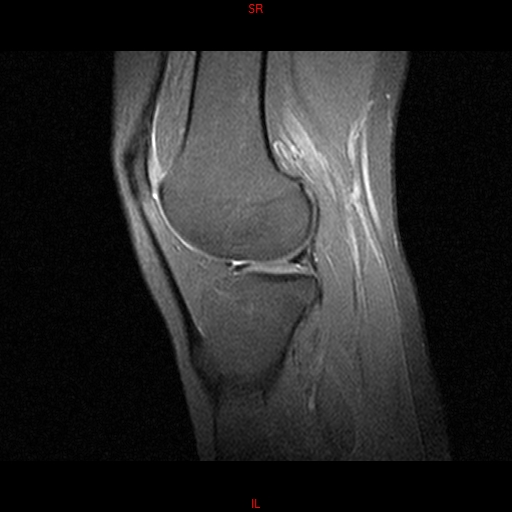

• RESONANCIA NORMAL RODILLA SAG DENSIDAD PROTONICA

• RESONANCIA NORMAL RODILLA SAG T1